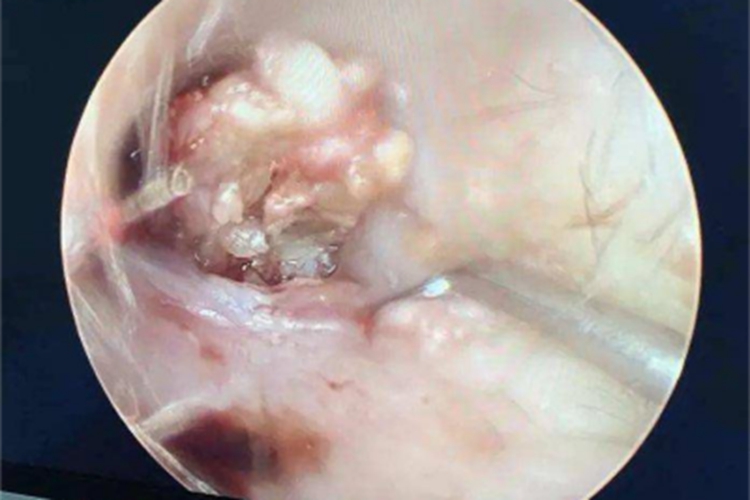

外耳道胆脂瘤检查可见外耳道内有肿瘤堵塞,呈黄色或白色,肿瘤表面被多层鳞片状物质包裹,无继发感染的小胆脂瘤可无明显症状,胆脂瘤较大时,可出现耳内堵塞感、耳鸣及听力下降。

外耳道胆脂瘤的治疗可用耵聍钩取出,如合并感染,应抗感染治疗。严重者应行手术治疗。具体如下:

无合并感染的胆脂瘤较易取出,可用耵聍钩取出。

合并感染时,应注意控制感染。但单纯地控制感染很难迅速奏效,只有全部或部分清除胆脂瘤后,方能促使炎症吸收。

感染严重、取出十分困难者可在全麻及手术显微镜下进行,同时遵医嘱全身应用抗生素控制感染。 术后应随诊观察,清除残余的或再生的胆脂瘤。

当病变广泛时,需行外耳道成型术,有时甚至需行乳突切除术。